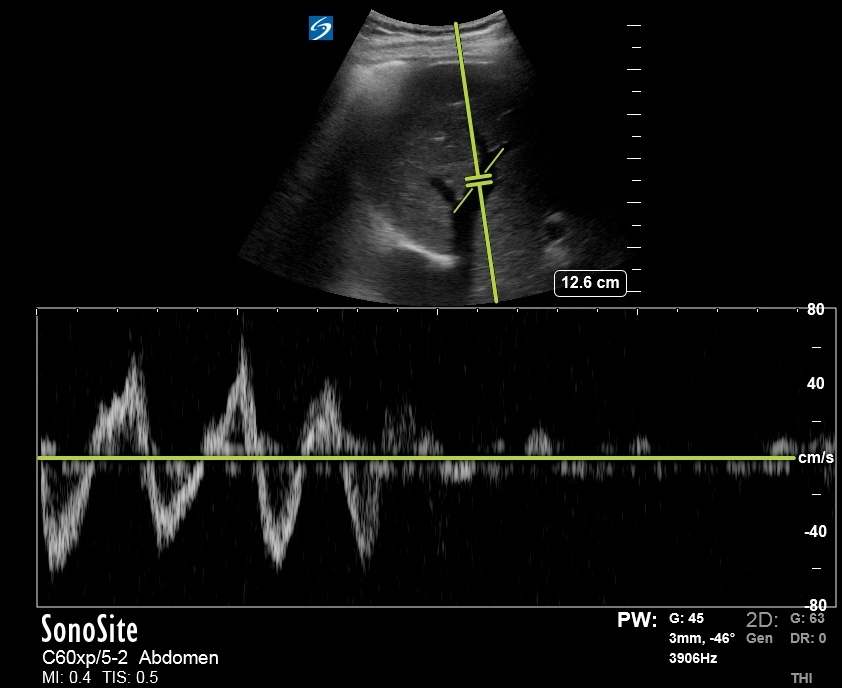

Another HV Doppler:

S Wave reversal better seen here. Thanks to @ArgaizR

S Wave reversal better seen here. Thanks to @ArgaizR